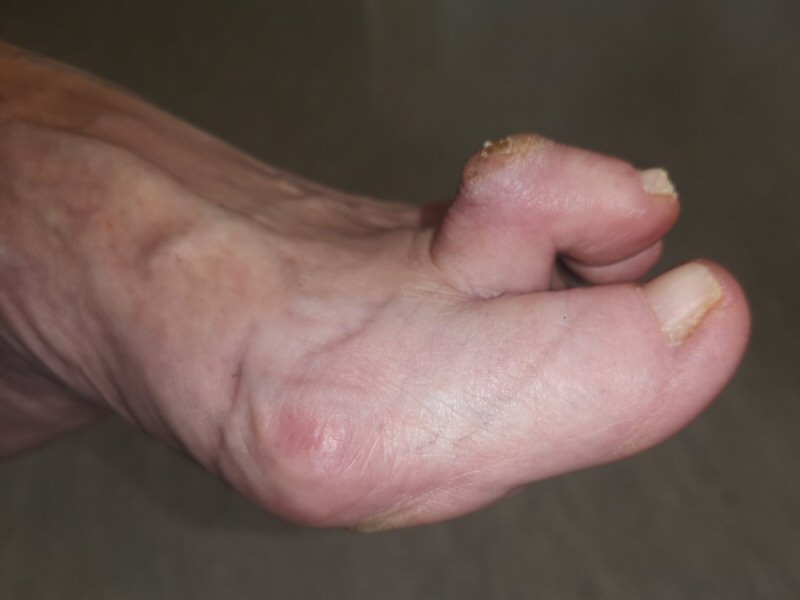

Hammartå: tå kontinuerligt flekterad i PIP-led

Röntgenbild resp. foto, hammartå dig 2

Klubbtå: tå kontinuerligt flekterad i DIP-led

Klotå eller mallettå: tå kontinuerligt flekterad i PIP- och DIP-led

Klavus: förhårdnad t.ex. dorsalt på PIP-led vid hammartå, kommer av kontinuerligt skav mot sko